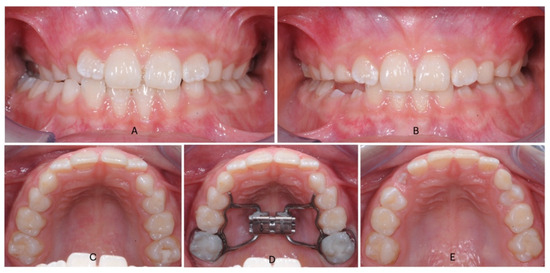

Figure 1.

Intraoral photos of Hyrax treatment in a patient with a contracted upper arch and a monolateral cross-bite: (A) (pre-treatment frontal view); (B) (post-treatment frontal view after overcorrection); (C) (pre-treatment occlusal view); (D) (occlusal view after cementation of Hyrax); (E) (post-treatment occlusal view).